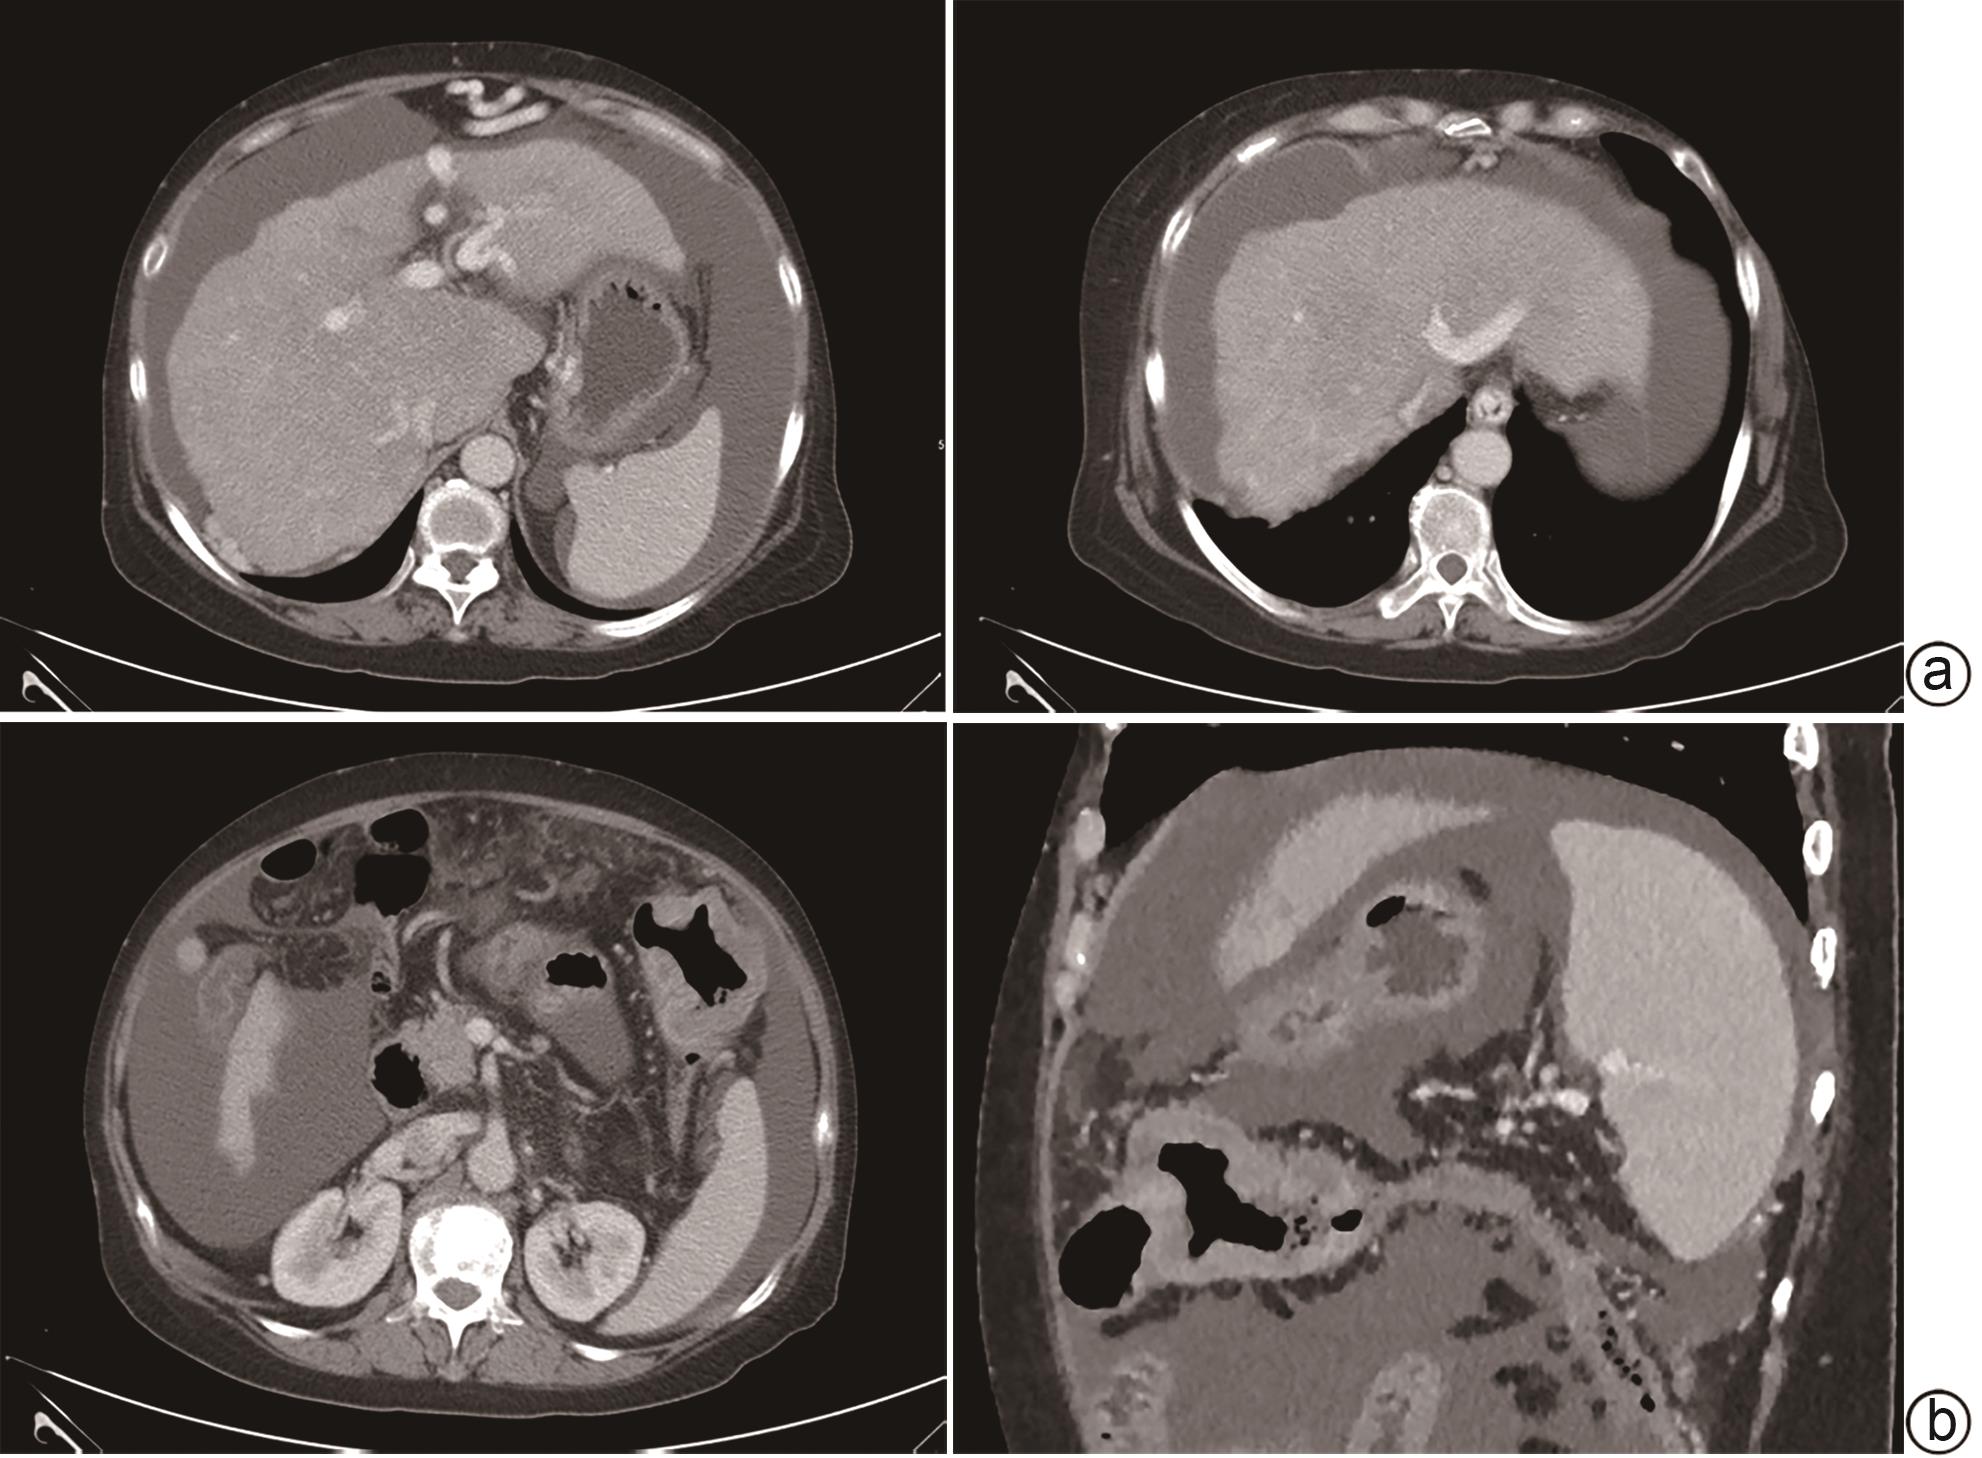

肝脏肿瘤

微波消融与手术切除治疗肝细胞癌合并肝硬化效果及安全性的Meta分析

骆建兴, 张扬, 向讷, 扈晓宇

2024, 40(9): 1807-1815. DOI: 10.12449/JCH240915

摘要(1209) HTML (353) PDF (2928KB)(64)

摘要:

目的  通过Meta分析系统评价微波消融(MWA)和手术切除(HR)在肝细胞癌(HCC)合并肝硬化中的有效性及安全性。  方法  本研究根据PRISMA指南完成,PROSPERO注册号:CRD42024509185。检索PubMed、Cochrane Library、EMBASE、Web of Science、中国知网、维普、万方数据库,时间均为从建库至2023年11月,搜索MWA对比HR治疗HCC合并肝硬化的随机对照试验(RCT)和队列研究,采用Stata 12.0软件进行Meta分析。  结果  共纳入3项RCT和5项回顾性队列研究,共953例患者。Meta分析显示:MWA的1/2/3/5年总生存率(OS)与HR相比无统计学差异(P值均>0.05)。MWA的1/2/5年复发率与HR相比无统计学差异(P值均>0.05)。MWA的3年复发率高于HR(RR=1.59,95%CI:1.08~2.33,P=0.017)。MWA的1/3/5年无复发生存率(DFS)低于HR(RR=0.94,95%CI:0.89~0.99,P=0.018,I2=0.0%;RR=0.84,95%CI:0.72~0.98,P=0.023,I2=25.4%;RR=0.75,95%CI:0.58~0.98,P=0.032,I2=34.6%)。但亚组分析表明,在RCT组,MWA的1/2/3年OS和1/3年DFS与HR相比无统计学差异(P值均>0.05)。MWA的术中出血量、手术时间、住院时间、不良反应及肝功能均优于HR(SMD=-2.31,95%CI:-2.64~-1.97,P<0.001,I2=3.1%;SMD=-3.38,95%CI:-4.05~-2.71,P<0.001,I2=73.8%;SMD=-2.54,95%CI:-3.27~-1.80,P<0.001,I2=92.8%;RR=0.42,95%CI:0.30~0.59,P<0.001,I2=0.0%;SMD=-1.43,95%CI:-1.89~-0.97,P<0.001)。  结论  MWA与HR在局部复发、DFS及OS方面无明显差异。MWA术中出血量更少,手术时间更短,不良反应更少,对肝功能影响更小,住院时间更短。